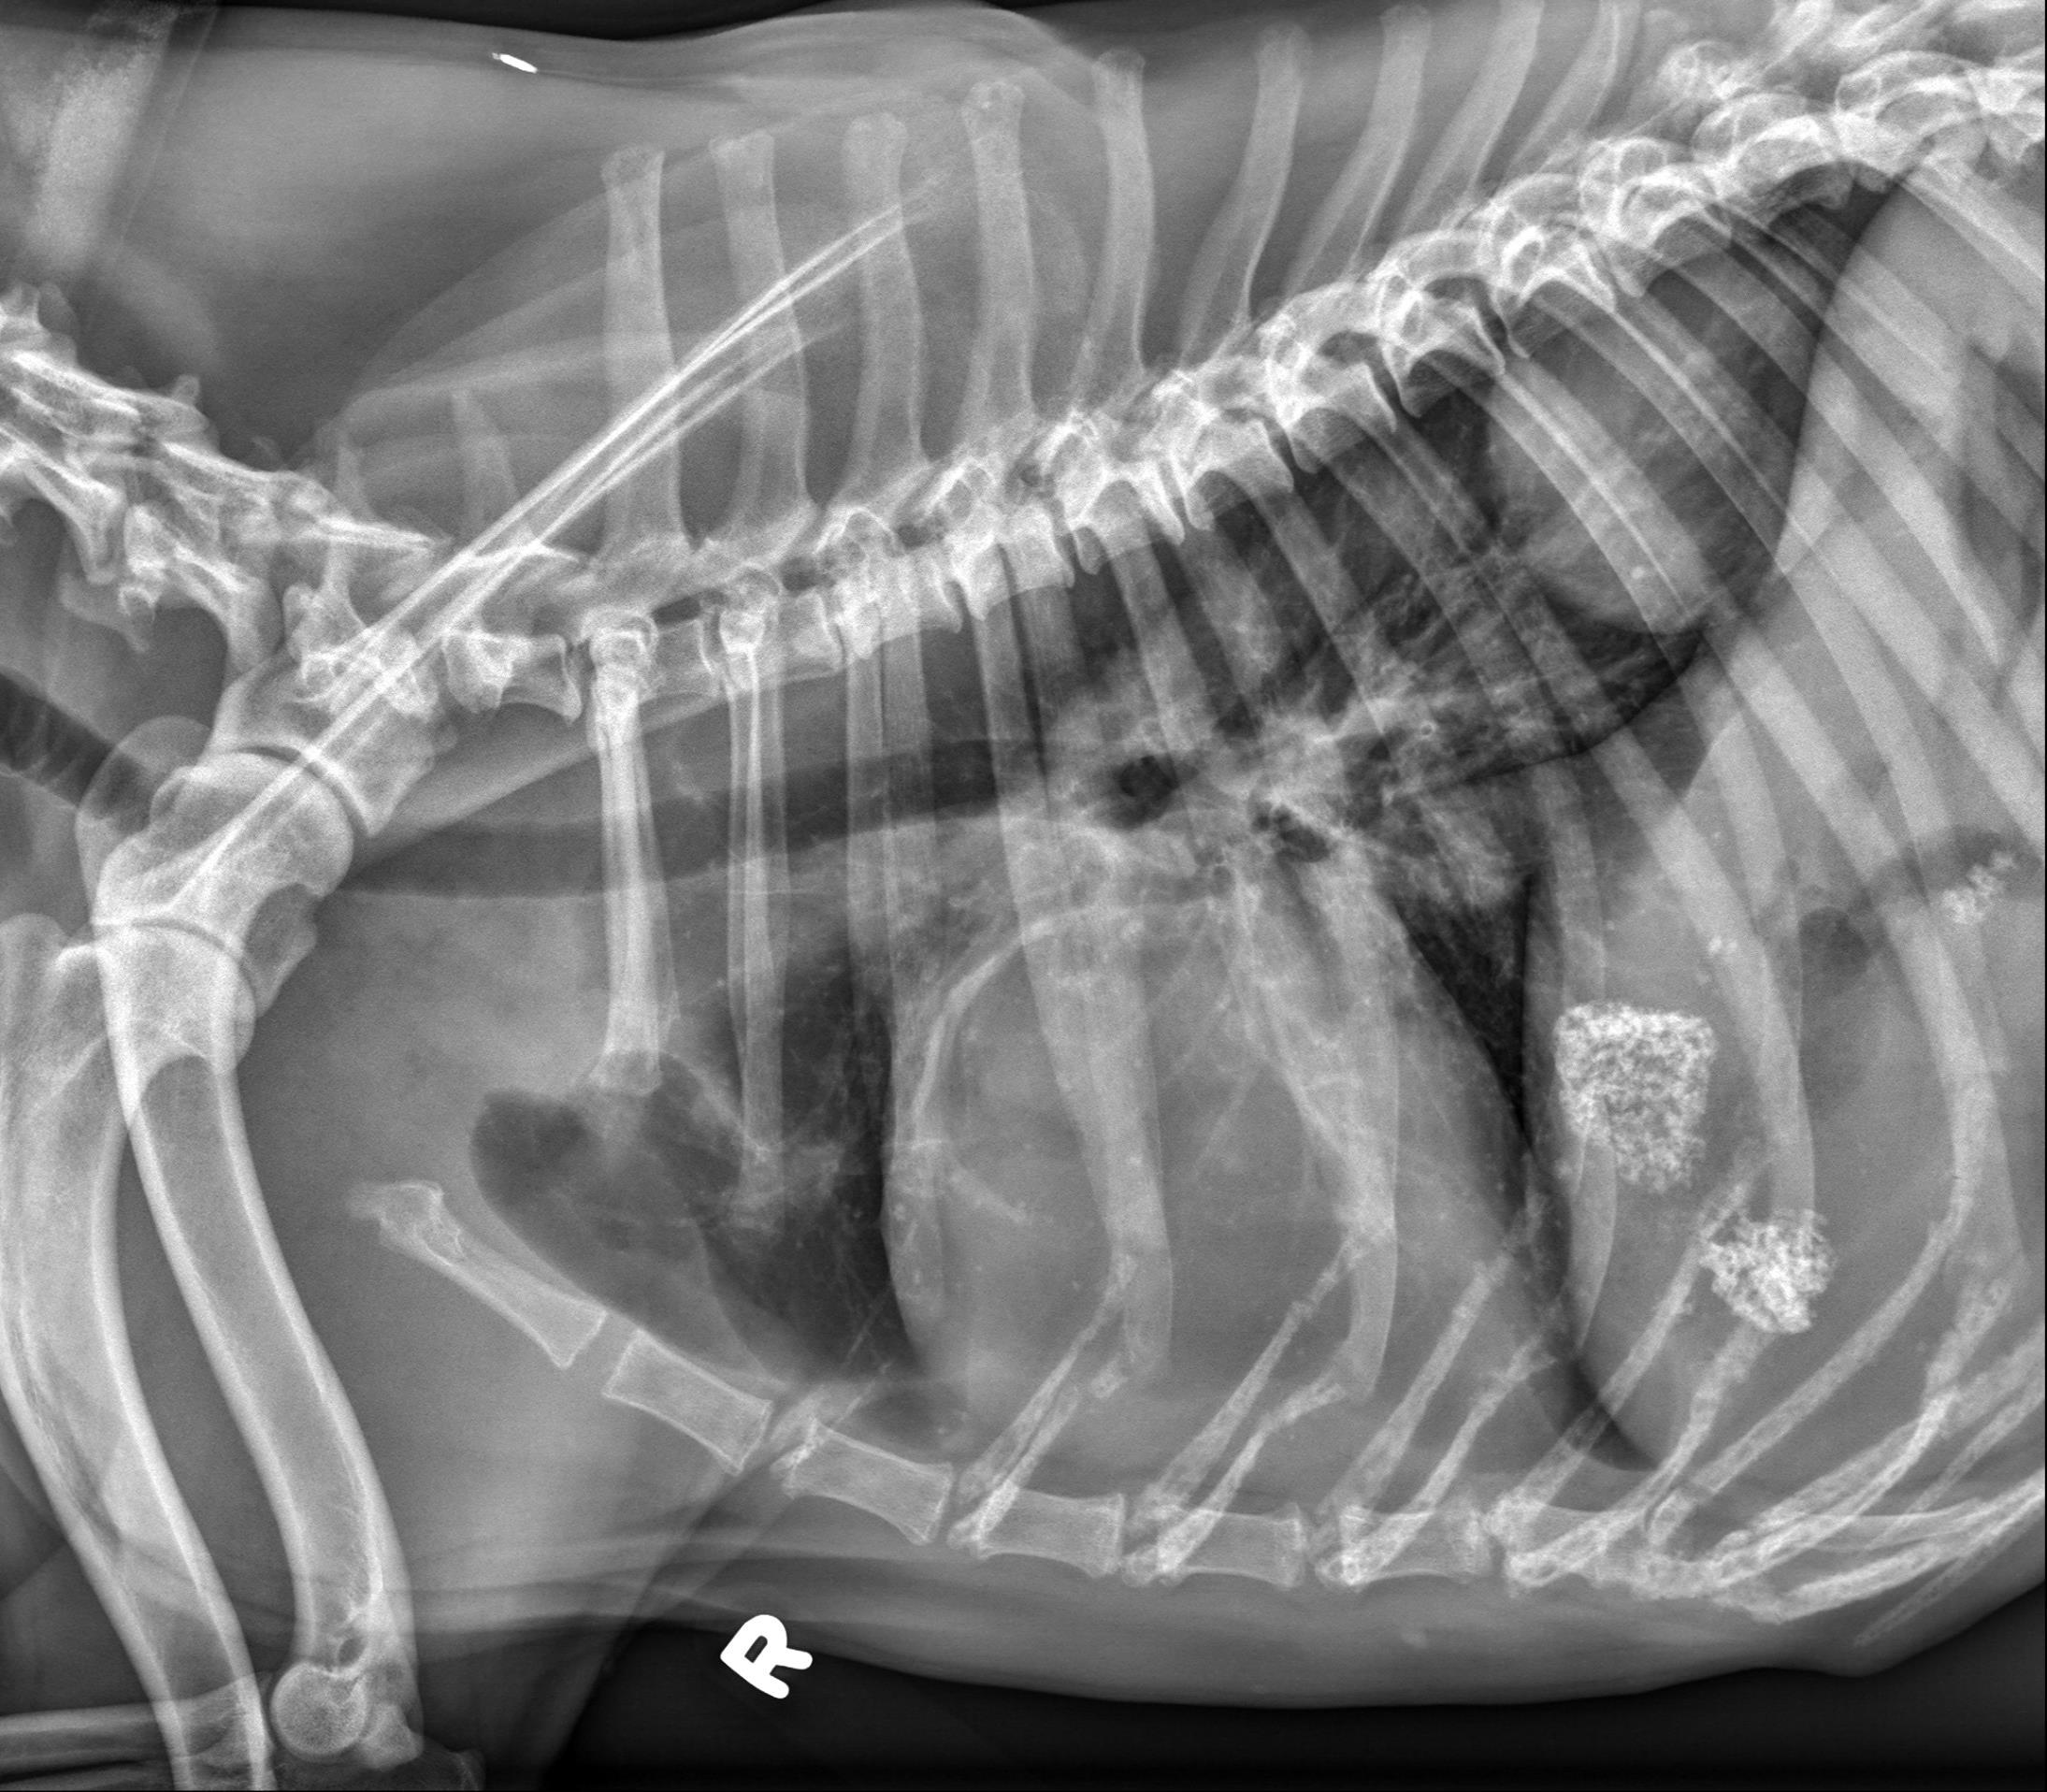

Thorax, 3 views:

There is an oval, well-circumscribed, soft tissue opaque mass associated with the most caudal dorsal aspect of the right caudal lung lobe. This mass measures approximately 7.0 x 7.0 x 6.6 cm (length X height X width) based on the left lateral and VD views (without correction for magnification).

There are additional multifocal pinpoint mineral opaque foci throughout the lung fields, consistent with incidental pulmonary osteomata.

On the right lateral view, there is a curvilinear mineral opacity superimposed with the cranial dorsal aspect of the cardiac silhouette at the level of the third intercostal space which is not identified on the other views and likely represents either incidental mineralization of a pulmonary vessel or artifact.

An additional faint curvilinear soft tissue opacity is superimposed with the cranial dorsal thorax from the 1st-2nd pair of ribs on both lateral views, consistent with incidental plate like atelectasis.

The cardiovascular structures, mediastinal structures, pleural space, diaphragm, and thoracic wall are normal. There is incidental caudal thoracic spondylosis deformans.

There are sharply marginated but irregularly shaped regions of heterogeneous mineral opacity superimposed with the right cranial aspect of the liver as well as the right cranial abdomen (superimposed with the expected location of the proximal descending duodenum on the lateral views and visible in the plane of the right 11th intercostal space on the VD view).

On both lateral views, there are faint branching gas opacities superimposed with the cranial abdomen which appear to be located within the hepatic parenchyma.

Single large right caudal lobar pulmonary mass. A primary lung tumor (pulmonary carcinoma) is most likely. No evidence of pulmonary metastatic disease.

Granular mineral opacities in the plane of the right cranial abdomen are most consistent with mineralization within the gallbladder and common bile duct. Dystrophic mineralization of hepatic parenchyma, pancreas, and/or regional abdominal fat are considered as alternate but less likely etiologies. The branching gas opacities in the plane of the liver are likely associated with the intrahepatic bile ducts.